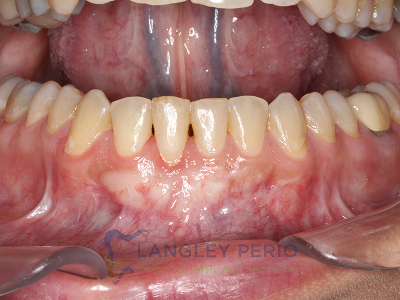

Case 1

Connective tissue grafting was performed to correct gingival clefting caused by over-aggressive toothbrushing